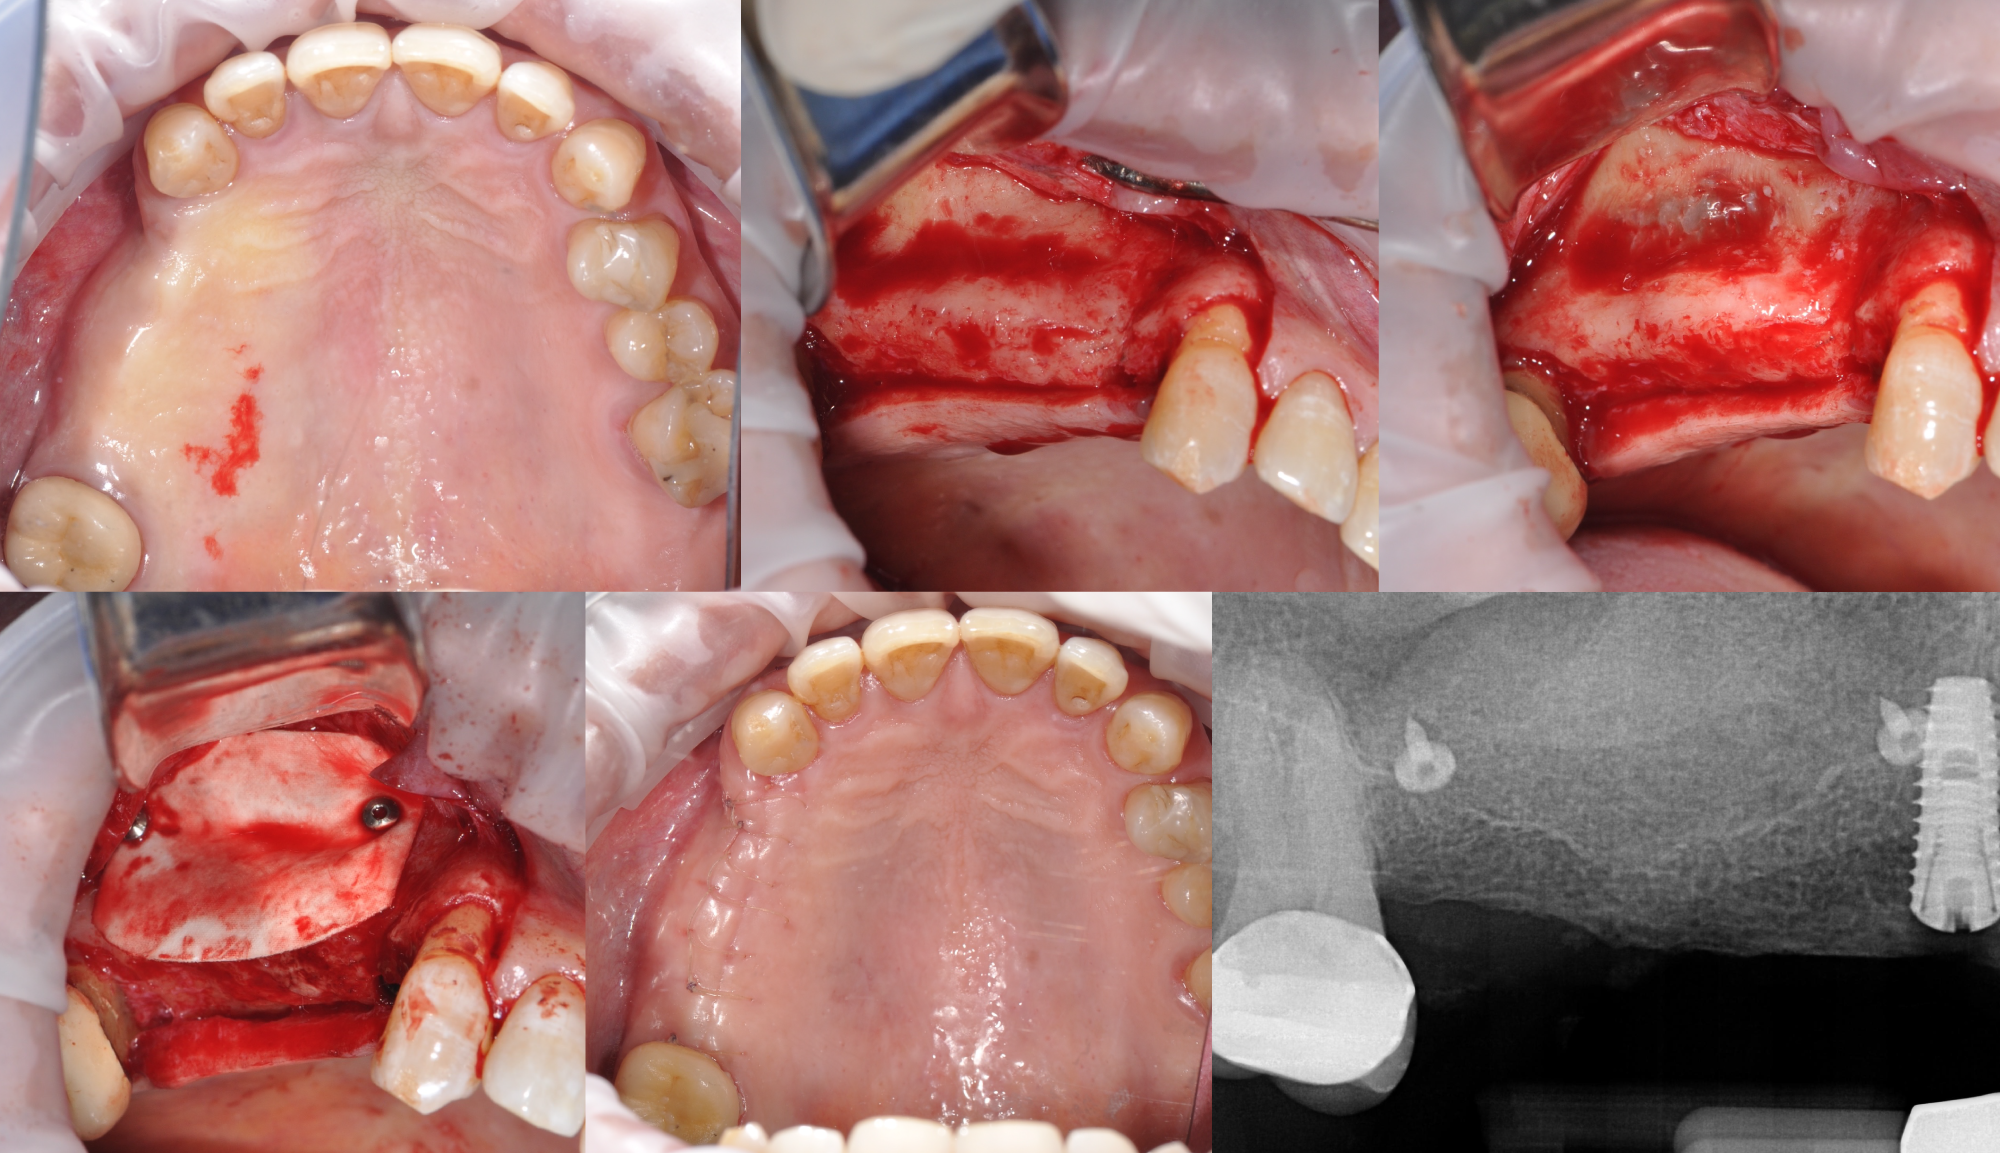

Director’s Clinical Cases

Director’s Clinical Cases